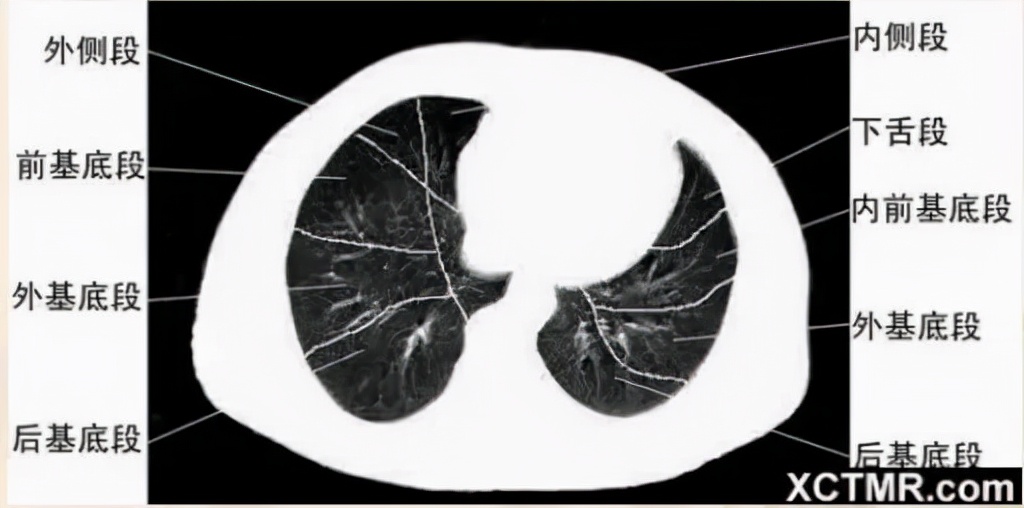

肺段划分